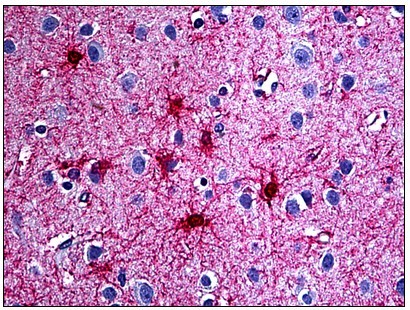

Supportive validation

- Submitted by

- Acris Antibodies GmbH (provider)

- Main image

- Experimental details

- Human Brain, Astrocytes: Formalin-Fixed, Paraffin-Embedded (FFPE)